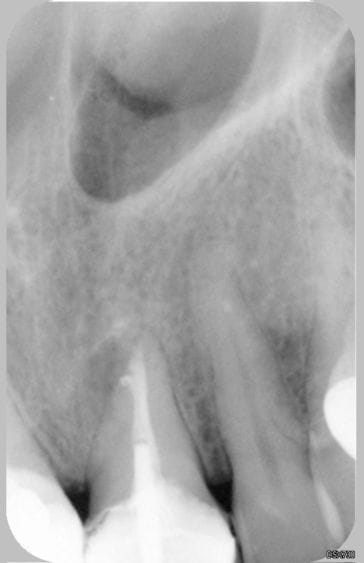

21 postop pomtkz - Eugenol

YEEEESSSSS!!! ça marche!

joli travail.

Alors t'as fait quoi pr retirer ce lentulo?:

tentative de ttt orthograde? Microendochir d'emblée? ou peut être les 2?

La rvg postop est J+combien....

La radio post op a été effectué environ 50 minutes après la préop.

Pas de chir apicale, juste un retrait par voie orthograde dans ce cas, après avoir bien vibrer le lentulo et être passé à coté avec une lime K15, je l'ai retiré en le saisissant le plus bas possible avec une pince de Steiglitz.

L'obturation est au Thermafil.

Bien sûr qu'il y a un peu de fierté, mais dans ce cas précis, je ne pense que cela était indispensable, car la lésion était plutôt latéroradiculaire et sans rapport avec l'instrument en question. Mais avant de se dire "je le laisse en place", il faut quand même essayer de le retirer (en tenant compte du rapport bénéfice/risque bien sûr). Et puis, c'est assez jouissif de retirer un fragment de 10 mm de long dépassant de 4 bons mm dans le périapex !